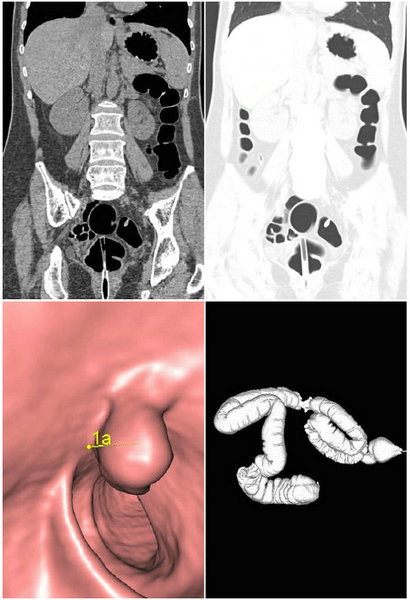

结肠CT充气造影技术:为大肠疾病提供了一种新的无创检查方法。结肠CT即利用CT采集结肠原始数据,在工作站使用计算机对其进行后处理,重建形成2D、3D图像,从而发现和诊断结肠病变。结肠CT成像已被证明与结肠镜检查的敏感性和特征性相当,被普遍作为一种预防、筛选结肠癌的经济有效的检查。

该检查方法对受检者耐受性好,不受肠道形态干扰,可观察肠腔内外及病灶周边组织信息,同时还可以观察腹腔其他脏器情况!我院影像中心科率先开展结肠CT充气造影,为大肠疾病的诊断提供了新的研究方向。